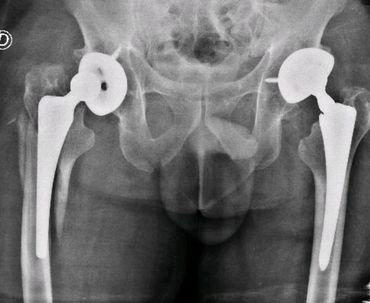

Revisión de cadera en un tiempo quirúrgico, por fractura periprotésica. Tallo de fijación distal, modular, osteosíntesis con lazadas de alambre y coti